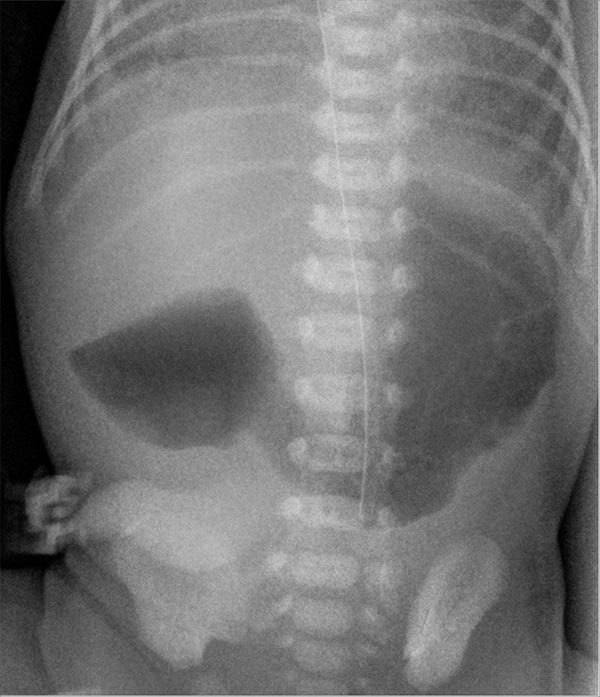

Abdominal X-ray imaging is crucial to the diagnosis of intestinal atresia. In duodenal atresia, the classic “double bubble” sign may be seen on abdominal X-ray in which both the stomach and first part of the duodenum are dilated. (See Figure 1.) In more distal cases of atresia, bowel distention also will be present. Other studies, such as upper gastrointestinal contrast studies, are less useful but may help rule out malrotation.46 Barium enemas may help differentiate between a large and small bowel obstruction in cases that are not clear.46 Additionally, during this workup, it is important to obtain basic laboratory work to assess for hypoglycemia, electrolyte abnormalities, and renal insufficiency.

Figure 1. Duodenal Atresia |

Source: Hellerhoff. Wikimedia Commons. https://commons.wikimedia.org/wiki/File:Duodenalatresie_0W_-_CR_ap_-_001.jpg |